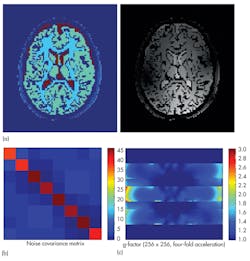

If it is not possible to achieve a perfect EM field distribution, it can be useful to evaluate the impact of an inhomogeneous EM field on the final image, and if compensation can be provided by the MRI sequence. Such compensation may require a dedicated MRI simulator such as the Juelich Extensible MRI simulator (JEMRIS).4 MRI simulators solve the Bloch equation, which describes the behavior of spins exposed to magnetic fields in a macroscopic way. In this way, MRI imaging can be simulated and relevant quantities such as a coil’s field of view (FOV), its g-factor for parallel imaging, and the noise covariance between the different channels can be calculated (Fig. 10). Integration between EM, thermal, and spin simulations provides a complete MRI simulation workflow. Of course, a simulation is only useful if it can be applied to the real world. Once a prototype of a coil has been constructed, it can be compared to actual measurements for that design. Homogeneous phantoms are widely available in MRI labs and easy to test, and their simple structure makes them simple to simulate, as well.

10. These images are outputs from JEMRIS for an eight-channel head coil, showing (a) full simulated MR images of the brain, (b) the coupling between each coil, and (c) its g-factor across a transverse slice.